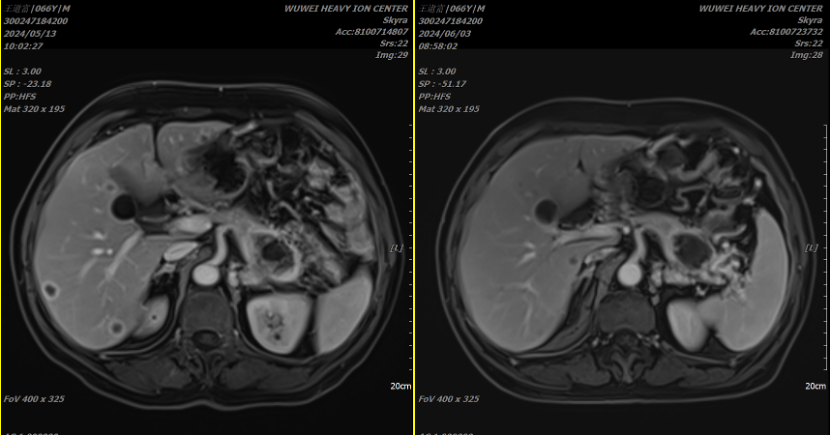

Medical History: The patient was admitted to the hospital in February 2024 due to abdominal pain without apparent provocation. A local abdominal CT scan revealed: A mass in the tail of the pancreas with malignant features, encasing the left renal vein and appearing to invade the left renal artery, stomach, and left adrenal gland. Several slightly hypodense nodules in the liver, suggest metastatic tumors. For further treatment, the patient visited our hospital on April 18, 2024. After admission, relevant examinations were completed. A pancreatic tumor biopsy indicated moderately differentiated pancreatic ductal adenocarcinoma. Immunohistochemical results showed: C-erbB-2 (0), CK19 (+), CK20 (-), CK7 (+), Ki-67 (index ≈ 5%), P53 (wild type), S100p (-). Gene testing detected a KRAS G12D mutation. An abdominal MRI scan suggested a mass in the tail of the pancreas, with local encasement of the left renal vein and unclear boundaries with the left adrenal gland, gastric wall, and left renal arteries and veins, most likely representing pancreatic cancer; multiple liver metastases were also observed. After excluding contraindications, the patient underwent carbon ion radiotherapy for pancreatic cancer and liver metastasis starting on May 1, 2024. The total dose for the pancreatic lesion was PTV 36Gy(RBE)/9Fx and PTVboost 22.5Gy(RBE)/5Fx; the dose for liver metastasis was PTV 40Gy(RBE)/10Fx and PTVboost 20Gy(RBE)/5Fx. Concurrently, the patient received chemotherapy with "gemcitabine + albumin-bound paclitaxel" on May 1 and May 8, 2024. A follow-up abdominal MRI scan after treatment indicated a decrease in the size of the lesion in the tail of the pancreas compared to the scan on May 13, 2024. Multiple liver metastases had also decreased in size for the most part.

Treatment Effect: After treatment, a follow-up abdominal MRI scan showed a decrease in the size of the pancreatic lesion and most liver metastases compared to previous scans.

Before treatment After treatment